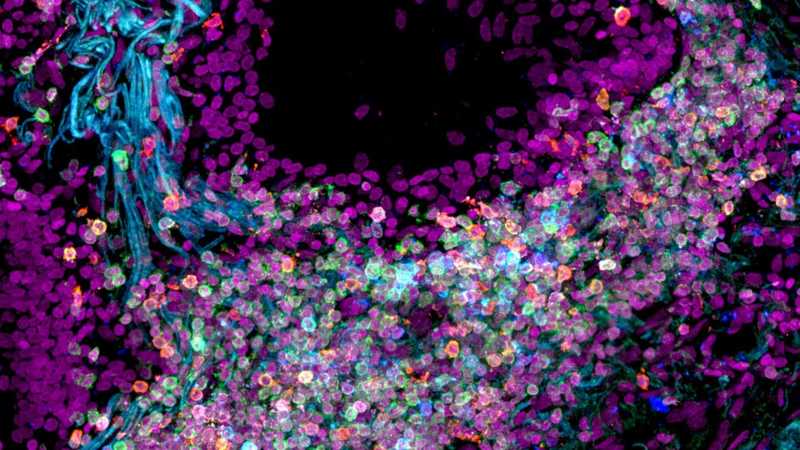

Ткань легких человека. Credit Nathan Richoz, University of Cambridge